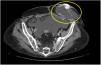

Hombre de 64 años, al cual se le realizó colectomía en 2018 secundaria a oclusión intestinal por cáncer de colon, además, como antecedente tiene cirrosis hepática secundaria a enfermedad hepática esteatósica asociada a disfunción metabólica, acudió a urgencias por sangrado agudo por sitio de estoma. El examen físico fue irrelevante y los exámenes de laboratorio revelaron anemia. Se observaron trayectos vasculares con evidencia de sangrado reciente a través de los bordes del estoma los cuales sangraban fácilmente (fig. 1). Se realizó inyección directa de cianoacrilato, consiguiendo hemostasia sin complicaciones (fig. 2). La tomografía de control muestra cianoacrilato en el estoma (fig. 3).